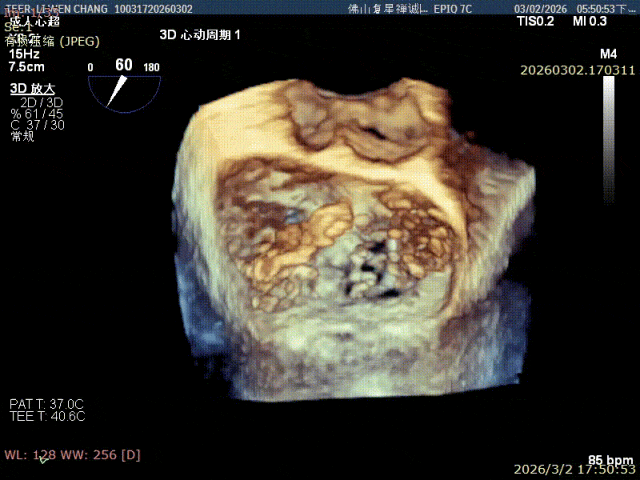

术前影像

3D 1区脱垂